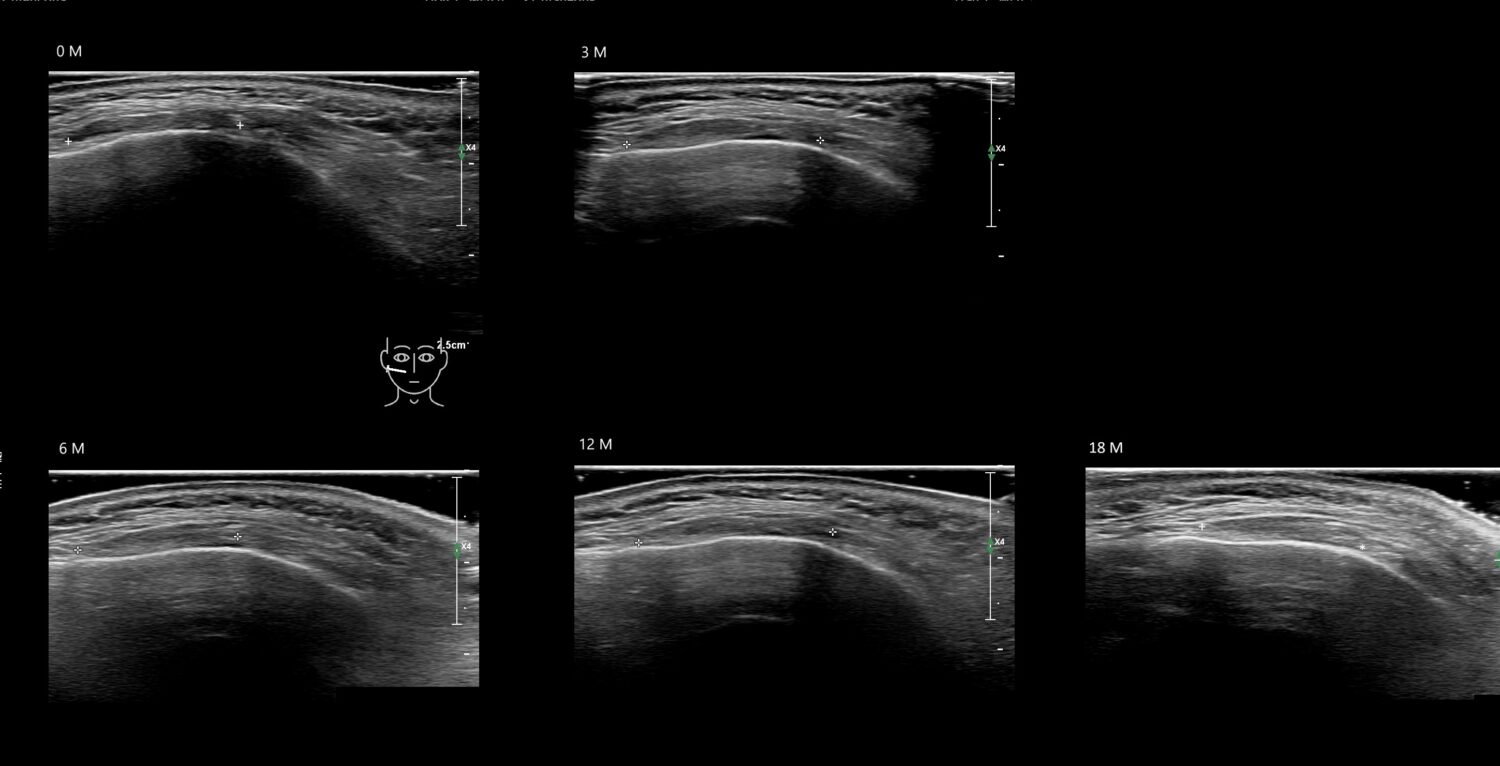

Fillers

Draw in the second image below where the fillers are located. To check if your answer is correct, swipe the first image to the right.